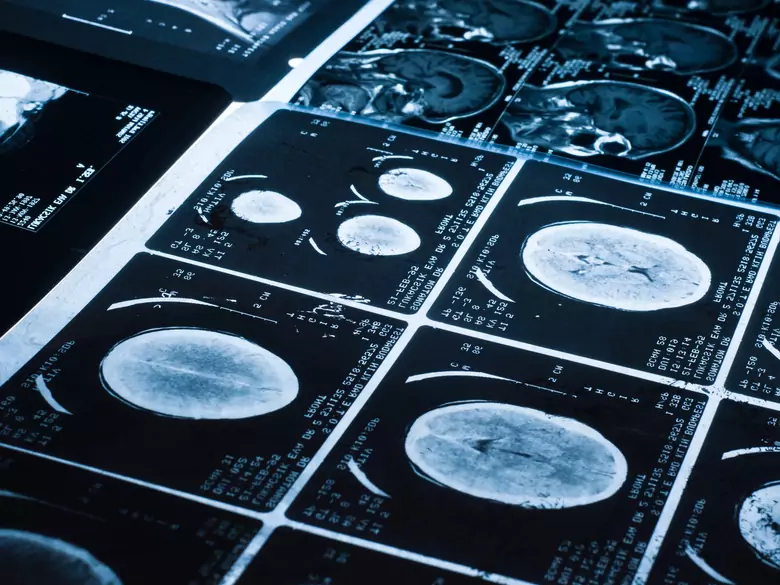

W niniejszym tekście opartym na opracowaniu “Radiation Risk to Children from Computed Tomography” autorstwa Brody A.S. i współpracowników (Pediatrics 2007, September, 677-682) przedstawiono fakty i zalecenia dotyczące ochrony radiologicznej przy badaniu TK u dzieci.

- dla TK głowy – 4 mSv (odpowiednik dawki z 200 zdjęć klatki piersiowej)